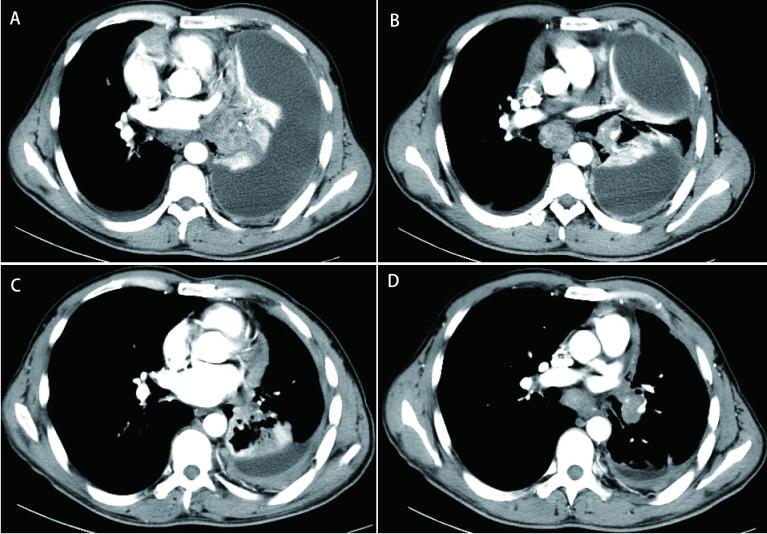

A 42 years old male patient was admitted to our department on July 3, 2015 for "intermittent cough, chest tightness for 2 months, diagnosed with lung adenocarcinoma for 1 day". Imaging examination showed a space occupying lesion in the left lower lobe of the lung, accompanied by mediastinal lymphadenopathy and left encapsulated pleural effusion. Bronchoscopic pathology showed non-small cell carcinoma, and adenocarcinoma was tentatively suggested.

1例42岁男性患者于2015年7月3日因“间断咳嗽、胸闷2个月,确诊肺腺癌1天”入院。影像学检查显示左肺下叶占位性病变,伴有纵隔淋巴结肿大及左侧包裹性胸腔积液。支气管镜病理显示非小细胞癌,初步考虑为腺癌。

诊断

左肺下叶腺癌T1bN2M1a Ⅳ期。荧光原位杂交(FISH)检测提示ALK(2p23)染色体易位。多西他赛+顺铂(DP)方案化疗2周期后疾病进展,换用培美曲塞+卡铂联合化疗6周期,之后采用培美曲塞单药化疗4周期。疗效评估:PR。2016年4月9日患者接受克唑替尼治疗。2019年8月发现多发颅内转移,给予全脑放疗。自2019年9月4日起口服恩扎替尼。截至2021年3月1日,患者随访情况良好。